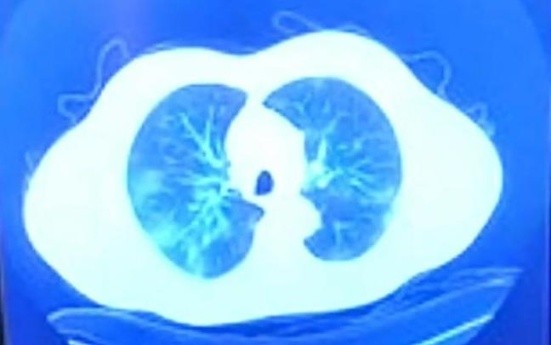

El gobernador de Baja California destacó la importancia de recibir atención médica a tiempo y comentó que deseaba mostrar la rápida evolución del coronavirus mediante imágenes que luego explicó un médico.

"(El coronavirus) afectó mis pulmones de la manera tan voraz y cómo realmente opera, trabaja y destruye el COVID", detalló Bonilla.

"Es para mí importante como gobernador enseñarles, de un pulmón sano, con todos los órganos de mi cuerpo funcionando, cómo un contagio como éste no le importa y te agarra de lo más débil".

Tomografía normal pulmón sano, del jueves 3 de diciembre.